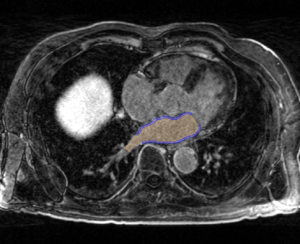

• The CARMA Center uses late gadolinium enhanced MRI (LGE-MRI) images to evaluate new patients, predict procedural success, and evaluate therapeutic outcomes. The MRI images for each patient are further accompanied by MR angiographic images (MRA) and manual segmentations of relevant structures. These images are acquired longitudinally over the course of a patient's evaluation, treatment, and follow-up (i.e. months or years). Registration is often necessary to compare images from different time points in a patient's treatment, different patients at the same stage of disease progression or treatment, and different image types. Registration is needed for a variety of combinations of common image types encountered at CARMA:

Pre-ablation LGE-MRI Image Post-ablation LGE-MRI Image Segmentation of LGE-MRI Image

Carma ex pre.png

Carma ex post.png

Carma ex pre seg.png

• Pre-ablation scans are acquired before the procedural. Bright portions in the LA wall are indicative of fibrosis; fibrosis scores are used to stratify and triage patients based on their Utah score.

• Post-ablation scans are acquired 3 months and later after the procedure. These scans have higher contrast (brighter regions) in the LA wall indicative of scaring from the ablation procedure.

• Segmentations will be binary label masks manually-contoured by experts at CARMA.